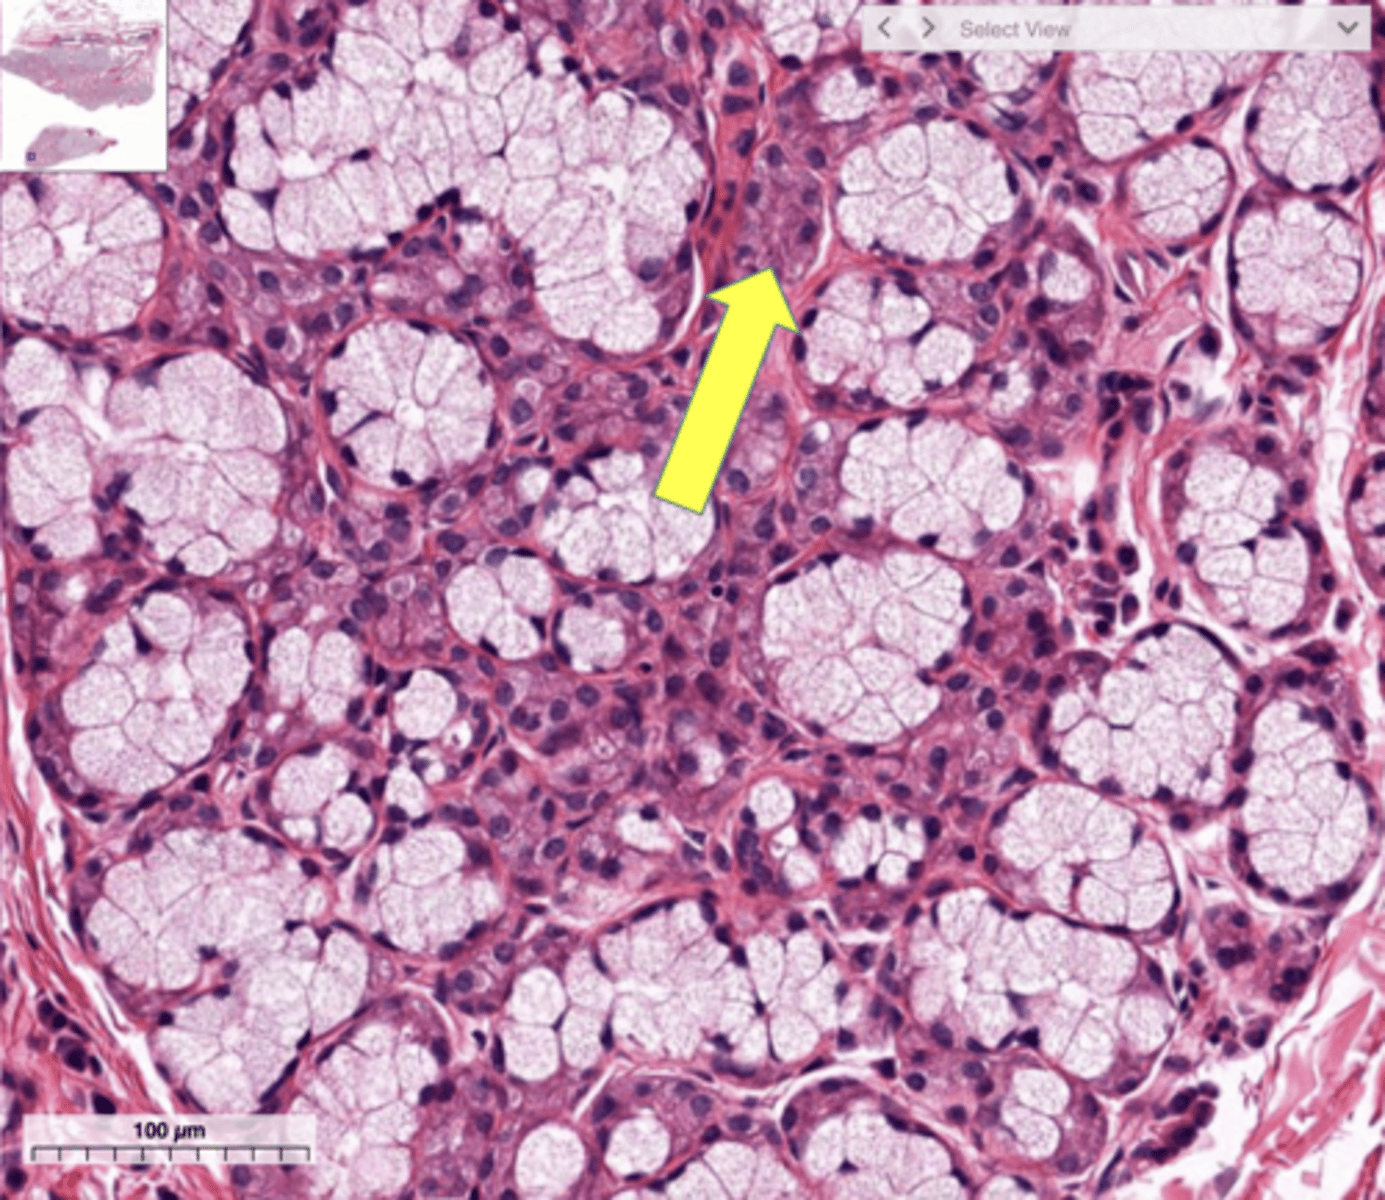

Pancreas

Acinar cells

Pancreatic islet

What cells make up the exocrine portion of the pancreas?

Pancreatic islets

What structure contains the endocrine portion of the pancreas?